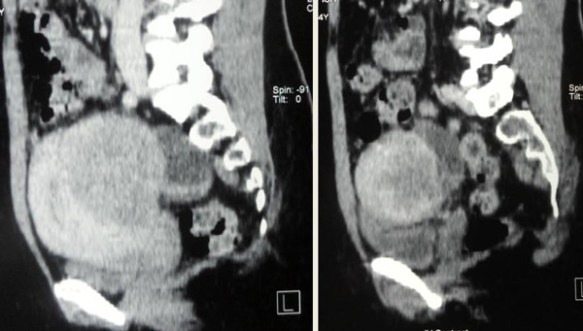

CT scan done on 18 January 2013 indicated a large uterus. There is a large posterior wall uterine myoma measuring 6.6 x 8.4 x 8.9 cm with central hypodensity likely to represent necrosis. It causes anterior displacement of endometrial and bladder depression.

Bilateral ovarian cysts. Right ovarian cyst measures 3.2 x 3.7 cm and left ovarian cyst measures 2.8 x 5.2 cm. There is an suggestion of left hydrosalphinx.

E-53--a

E-53--b